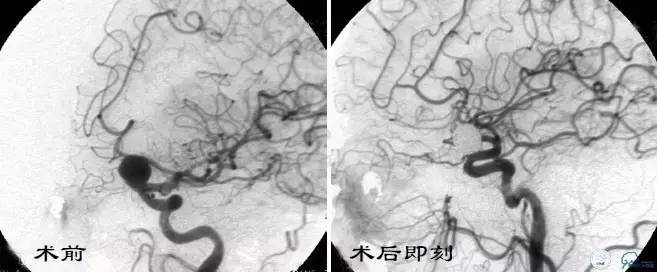

Case3 左ICA床突旁动脉瘤术后复发

术前VS术后即刻